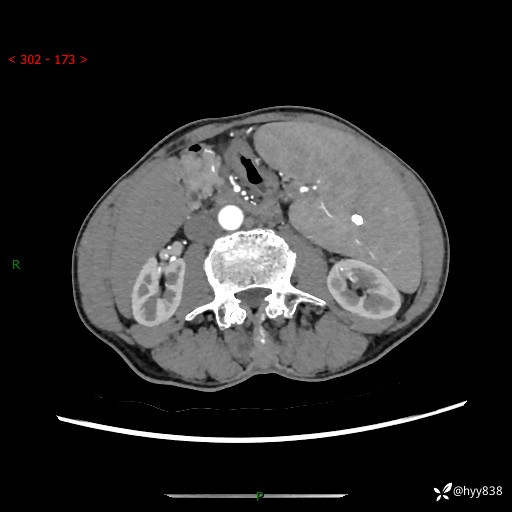

老年男性,脾大并脾脏弥漫粟粒状低密度,淋巴瘤 VS 肉芽肿 VS 血管瘤---结果公布

简要病史: 患者于3月前无明显诱因出现脾大,伴腹部轻微不适,具体不详,无腹痛、腹泻、腹胀,无头晕、头痛、乏力,无恶心、呕吐、呕血,无胸闷、气短、胸痛不适

上腹部CT平扫+增强